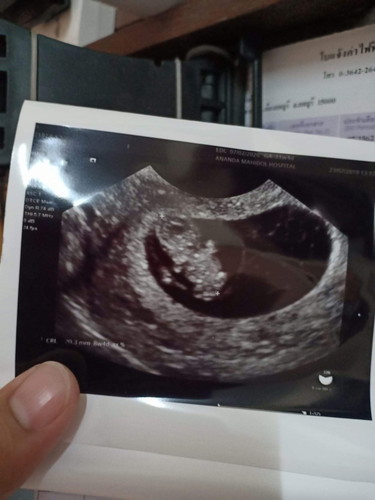

หลังจากเข้าใจผิดว่าตัวเองตั้งท้องได้11w วันนี้ไปซาวผ่านช่องคลอดหมอบอกน่าจะ 8wคงจะคลาดเคลื่อนกับประจำเดือน ตอนแรกตกใจมากเพราะซาวหน้าท้องไม่เห็นน้องเจอแต่ถุง วันนี้เจอน้องแล้วพร้อมเสียงหัวใจเต้นและปกติดีค่ะ